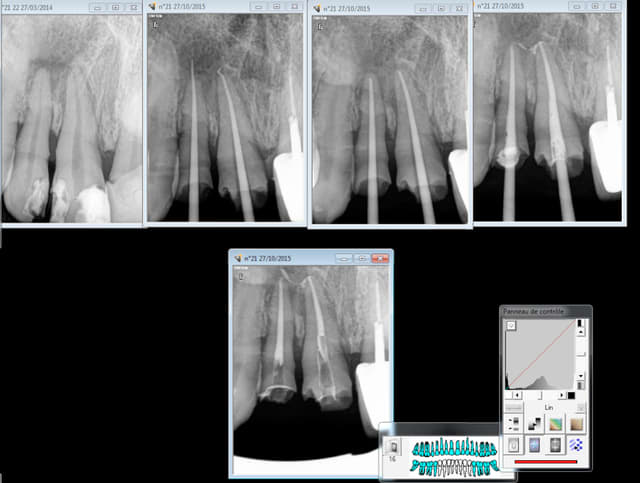

j'en ai vu en 38 ans , mais ça jamais

abces genre parulie volumineuse en vestibulaire de 37 pas fistulisée

le 3D montre la racine mésiale de 37 au milieu d'un patouillou pathologique remontant jusqu'à la furcation

diagnostic évident : nécrose de 37 avec abcès

j'attaque pour traiter , sans anesthésie et la patiente m'arrete ... je la crois (je la connais depuis 38 ans) je me dis qu'il reste un peu de vitalité sur la racine distale

anesthésie ... merci QS5 en distal et à distance de l'infection, et au premier coup dans la pulpe ... du sang ... une goutte , pas un jaillissement j'ouvre et je trouve une pulpe parfaitement vivante ... je fais mon endo et la vitalité est confirmée à l'obturation : pas un poil de depassement de ciment dans la lésion

pour les puristes, la digue a été déposée pour la radio .

moralité : même les signes objectifs peuvent être interprétés avec subjectivité en fonction de nos cognitions .

Joli endo, mais l'infection ne viendrait elle pas de la racine distale de la 36?

L'apex ne parait pas hyper sympa !!

+1

j'ai l'impression que tu as encore du boulot ..

bien sur qu'elel vient de 36 puisque 37 était vivante

ce qui est sidérant c'est tout donnait le sentiment que la mésiale de 37 était directement impliquée dans le processus , ce qui n'était pas le cas

j'ai déjà vu des trucs comme ça en antérieur mandibulaire avec des dents vivantes qui plogent dans les lésions , mais jamais sur des molaires, et jamais avec atteinte de la furcation d'une dent vivante

tellement sur de moi que si je n'avais pas connu la patiente quand elle a manifesté sa douleur , je l'aurais foutue dehors en lui disant qu'elle ne pouvait pas avoir mal